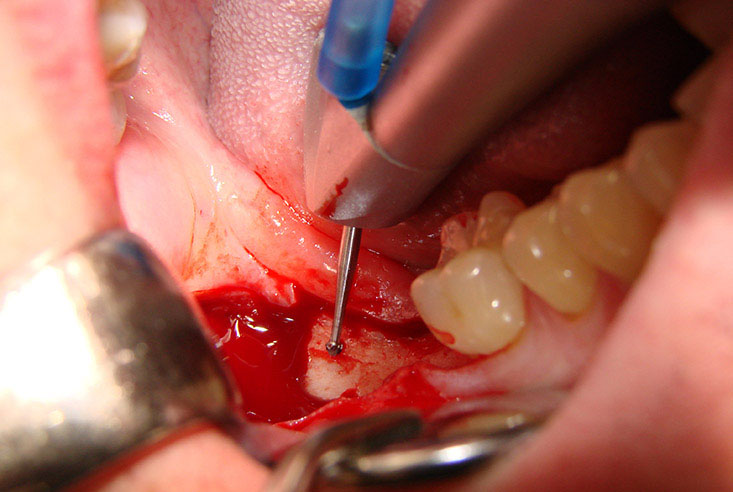

Trước kia, răng khôn được nhổ bỏ chủ yếu bằng cách dùng kìm, khoan đục truyền thống. Thời khắc nhổ bỏ răng trở thành nỗi ám ảnh với nhiều người. Thế nhưng, hiện nay, với sự phát triển của công nghệ hiện đại, phương pháp nhổ răng hiện đại dùng máy siêu âm Piezotome đã ra đời giúp khách hàng an tâm hơn với rất nhiều ưu điểm đáng nói:

Nhanh hồi phục vết thương, ít biến chứng

Piezotome rất thích hợp với những ca nhổ răng khôn khó như là mọc lệch 90 độ, mọc ngầm, răng nhú lên khỏi lợi rất ít.

Ưu điểm chính của phương pháp nhổ răng khôn siêu âm này là khả năng cắt chính xác và có chọn lọc của Piezotome, giúp giảm thiểu tổn thương tối đa cho các cấu trúc mô mềm, giảm chảy máu trong quá trình phẫu thuật. Đồng thời, phẫu thuật răng khôn hàm dưới bằng máy phẫu thuật siêu âm còn kiểm soát quá trình viêm tốt hơn nên các tổn thương được phục hồi nhanh chóng, ít nguy cơ biến chứng trong và sau phẫu thuật cho bệnh nhân.

Bớt đau đớn và căng thẳng

So với các phương pháp truyền thống dùng panh, kìm để nhổ răng thì khi sử dụng phương pháp dùng máy siêu âm sẽ giảm bớt đau đớn cho bệnh nhân. Dưới tác động của máy siêu âm, phần nướu, mô xung quanh chân răng khôn số 8 được lấy ra một cách đơn giản và nhẹ nhàng.

Ngoài ra, đầu cắt siêu âm tạo ra ít tiếng ồn hơn nên giúp người bệnh giảm bớt căng thẳng trong quá trình nhổ răng, tổn thương ít hơn so với dùng đục, khoan siêu tốc.